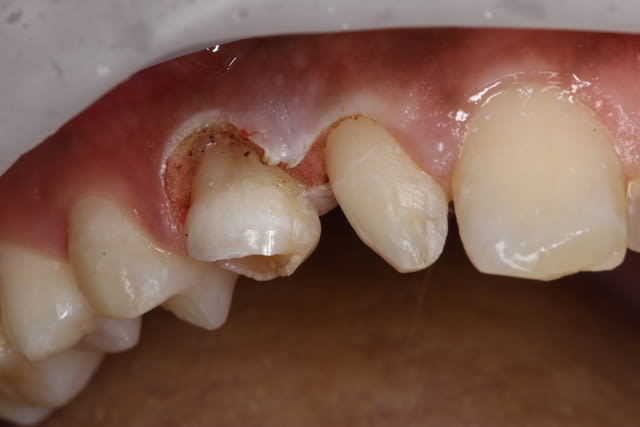

Bon je n'avais pas mis la digue sur cette 14 en 2009. A votre avis la peche en 2014 est elle due à ca ? Moralité toujours mettre de l'angulation dans les radios.